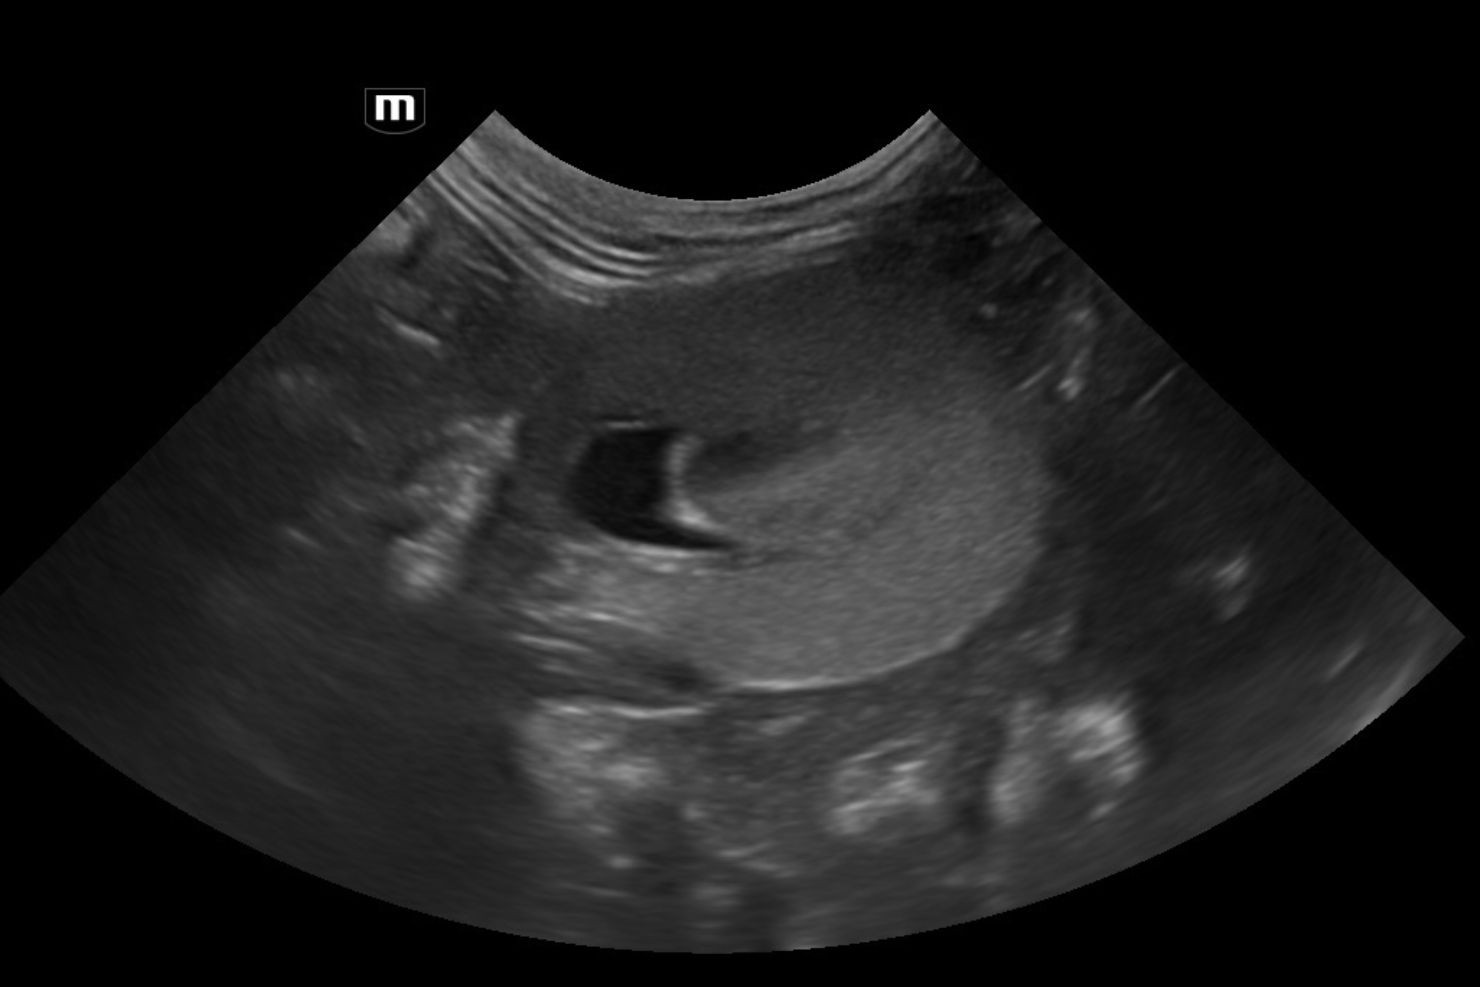

Fortgeschrittene strukturelle Veränderungen zeigen sich bei Katzen durch eine fleckige, hochgradige Hyperechogenität, meist verbunden mit einer anfänglichen Schwellung der Nierenrinde. Es ist keine Unterscheidung der Rinden-Mark-Grenze mehr sichtbar; das Nierenbecken ist erweitert. Daran können wir erkennen, dass diese Niere definitiv schon längere Zeit ein Problem hat. Wenn auch radiäre, hyperechogene Streifen sichtbar sind, ist das prognostisch besonders ungünstig. Eine Verdickung der Nierenrinde ist sowohl bei Hunden als auch bei Katzen ein Alarmsignal – eine Niere, die bereits länger schlechter arbeitet, wird kleiner und höckrig. In weiterer Folge erscheint dann auch das Nierenbecken geringgradig dilatiert. Hier hilft es, beide Nieren zu vergleichen. Die Messung der Breite des Nierenbeckens sollte allerdings nur im Querschnitt erfolgen.

Der erste Ultraschallbefund ist wichtig, um Erkrankungen wie zum Beispiel die polyzystische Nierenerkrankung ausschließen zu können. Auch Begleiterkrankungen wie eine urämische Gastritis sehe ich bei fortgeschrittener CNI häufig – das ist natürlich prognostisch ungünstig. Daher empfehle ich, die Ultraschalluntersuchung wenn möglich durchzuführen, sobald erste klinische Symptome wie Polyurie und Polydipsie auftreten und möglicherweise die Nierenwerte noch gar nicht auffällig erhöht sind. Für Verlaufskontrollen sind die Kontrollen der Blutwerte wichtiger. Die Ultraschalluntersuchungen sollten dann je nach Ausgangslage individuell vereinbart werden.

Größere Konkremente in der Niere sehe ich vergleichsweise selten. Was die Hydronephrose betrifft, so gibt es leider in der Veterinärmedizin keine Klassifikation der verschiedenen Stadien; die Humanmedizin hat im Gegensatz dazu viel genauere Kriterien festgelegt. Meiner Erfahrung nach kann sich eine etwaige Hydronephrose nach chirurgischer Intervention wieder erholen, wenn etwa eine Obstruktion durch ein Konkrement im Ureter vorlag, solange noch eine Rinden-Mark-Grenze beziehungsweise größere Anteile der Rinde vorhanden sind.